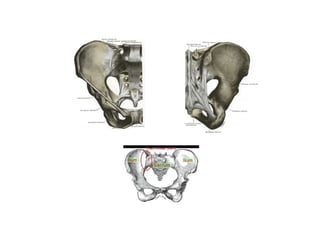

• Módulo 17 - Quadril